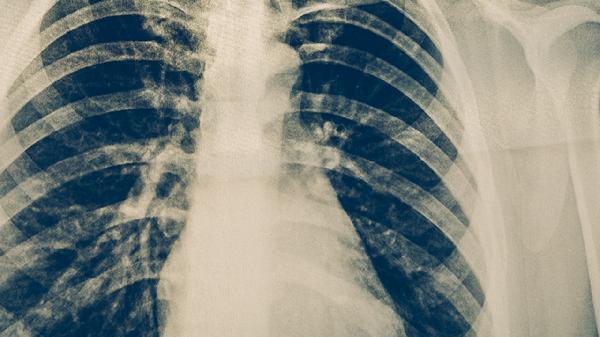

肺結核與肺癌并存的治療

肺結核與肺癌并存時需采取綜合治療策略,主要包含抗結核治療、腫瘤針對性治療及支持治療。兩種疾病并存可能增加治療難度,需由呼吸科、腫瘤科等多學科團隊協(xié)作制定個體化方案。

兩種疾病并存易導致肺部感染、呼吸衰竭等并發(fā)癥。需定期進行痰培養(yǎng)、胸部CT評估,出現(xiàn)發(fā)熱、咯血等癥狀時及時排查感染加重或腫瘤進展。結核病灶周圍纖維化可能影響放療定位,需通過呼吸門控技術提高精度?;熀罅<毎狈ζ谛桀A防結核復發(fā),必要時給予預防性抗結核治療。合并糖尿病等基礎疾病者需強化血糖控制。